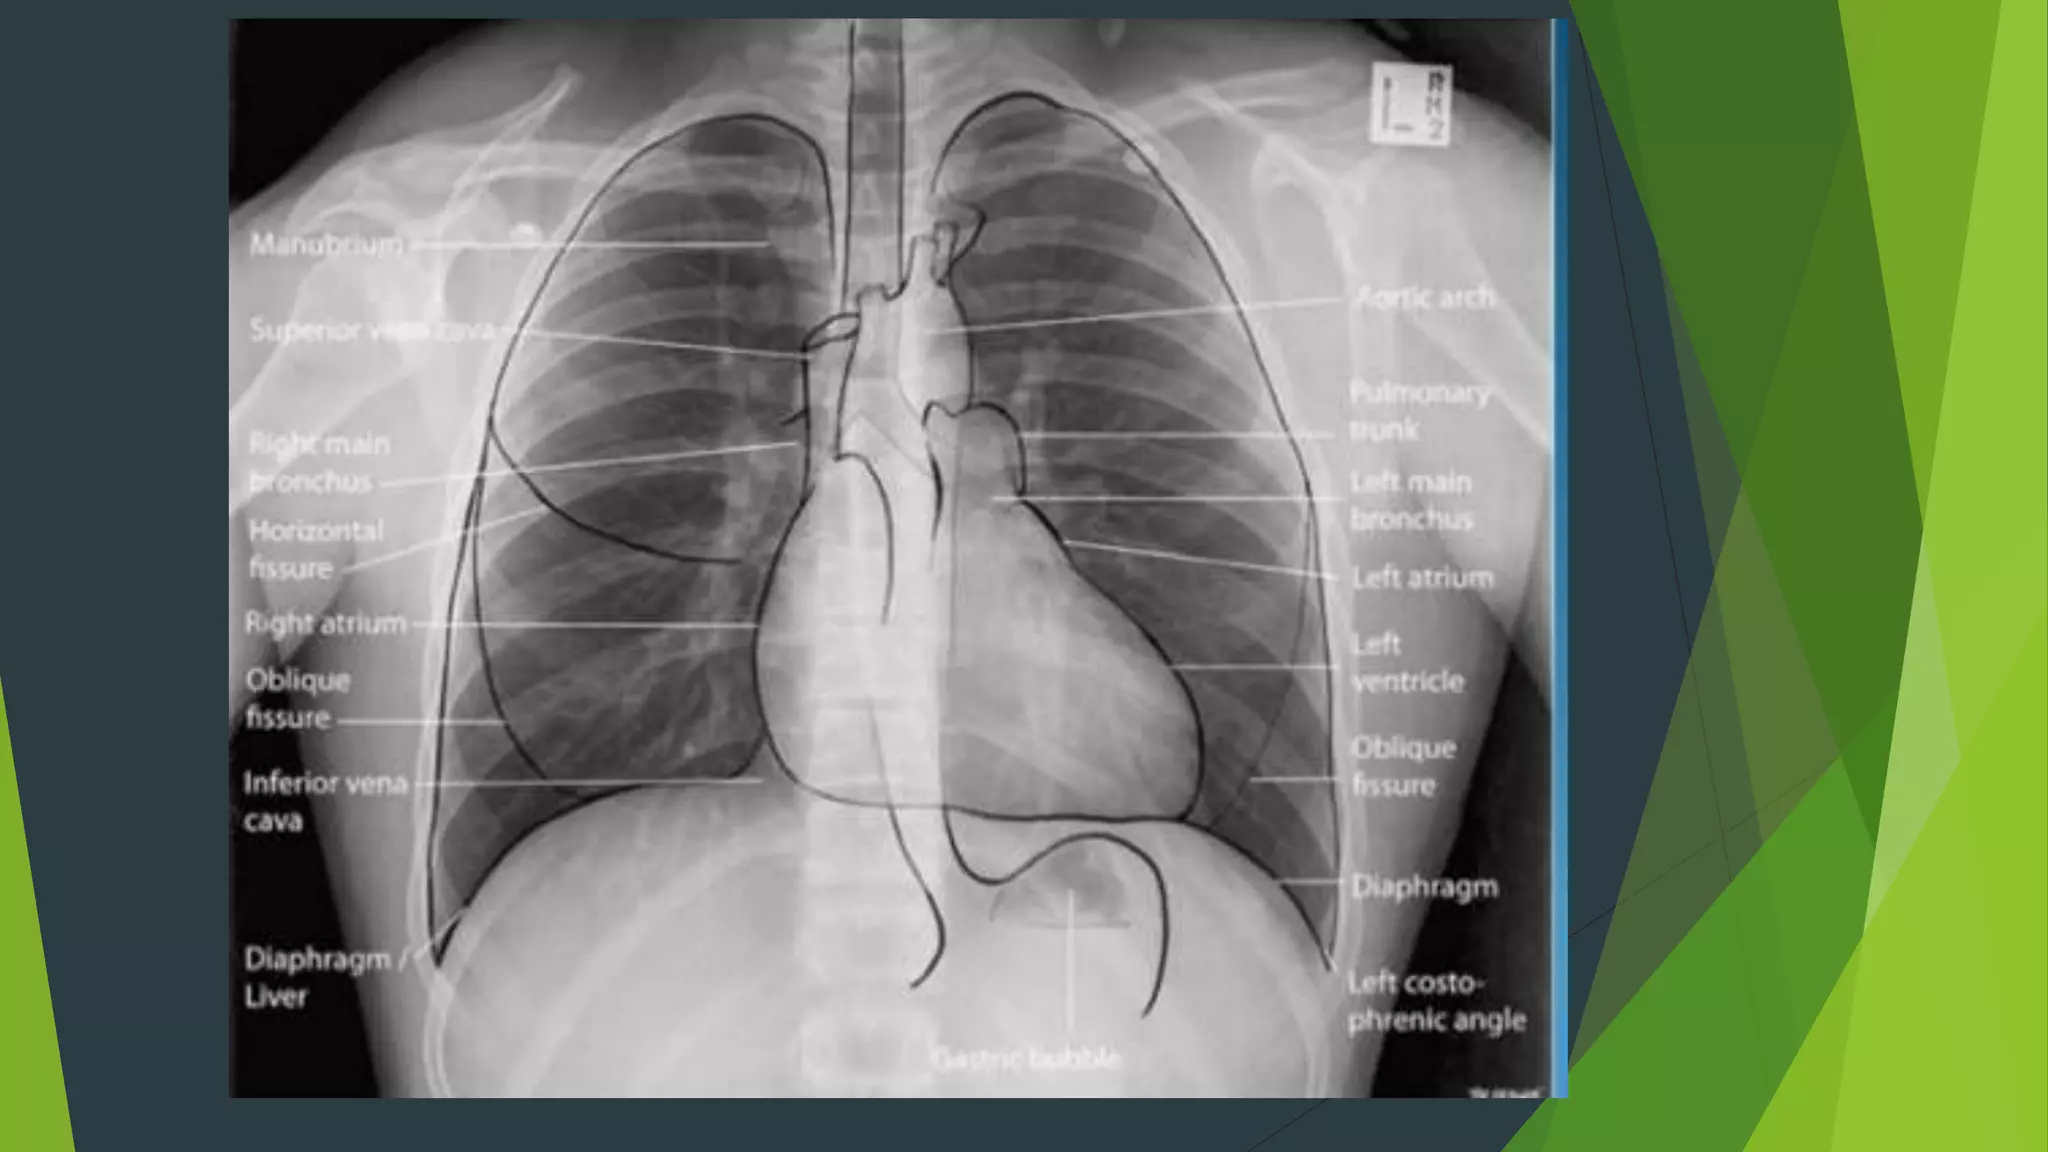

1. Hoàn toàn thẳng: bờ trong xương đòn đối xứng nhau qua

đường giữa Cân xứng : mức hơi dịch ở túi hơi dạ dày, hai

xương bả vai tách ra khỏi lồng ngực.

2. Hít vào đủ sâu: cung trước xương sườn 6 - 7 trên vòm

hoành. Cung sau ở xương sườn 10 trở xuống

3. Độ đối quang tốt : Thấy được 3 - 4 đốt sống ngực

trên,thấy được mạch máu sau tim gan, thấy mạch máu

cách ngoại vi phổi 1-2cm.

Giải phẫu hệ hô hấp